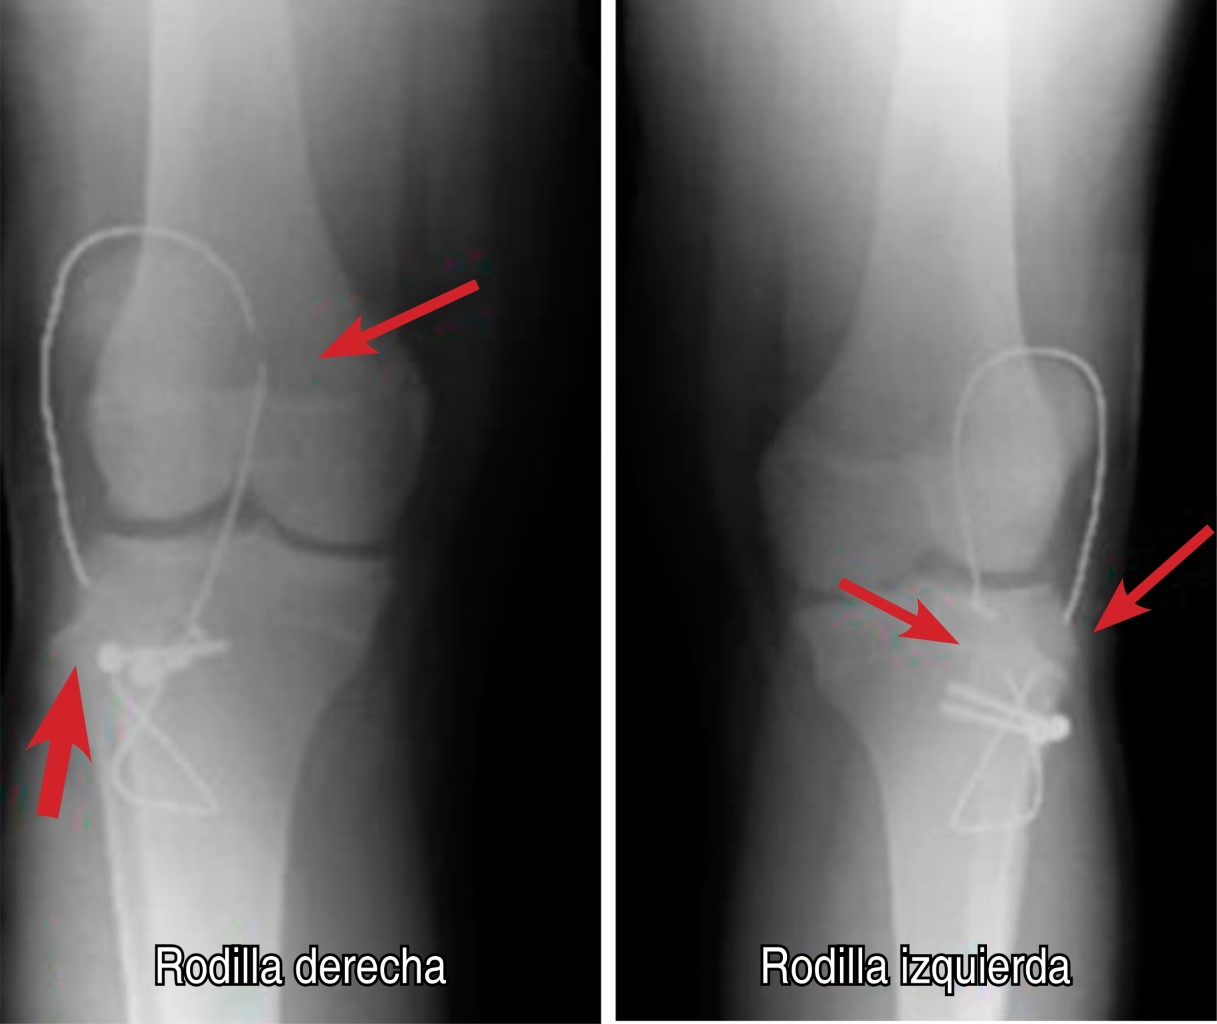

Se realiza intervención quirúrgica, encontrándose lesión de retináculo medial bilateral, tendón rotuliano íntegro, tuberosidades tibiales se fijan con dos tornillos de esponjosa 4.0, arandelas y bandas de tensión con alambre 1.2 mm a 45o de flexión (Figura 2). Movilización activa a 60o de flexión y 0o de extensión de rodillas en postquirúrgico inmediato. No es posible retirar bandas de tensión a la sexta semana, aun así el paciente ya contaba con arcos de movilidad completos y deambulación sin ayuda de muletas. Tres meses y medio postquirúrgico inicia con dolor repentino e imposibilidad a la deambulación, estudio radiográfico muestra fatiga de bandas de tensión y tuberosidades tibiales con datos de consolidación (Figura 3), por lo que se retira material de osteosíntesis. Al año de evolución se encuentran fracturas consolidadas (Figura 4), sin deformidad clínica en rodillas (Figura 5), sin dolor residual y realizando actividades deportivas.

Figura 2

Figura 3

Figura 4